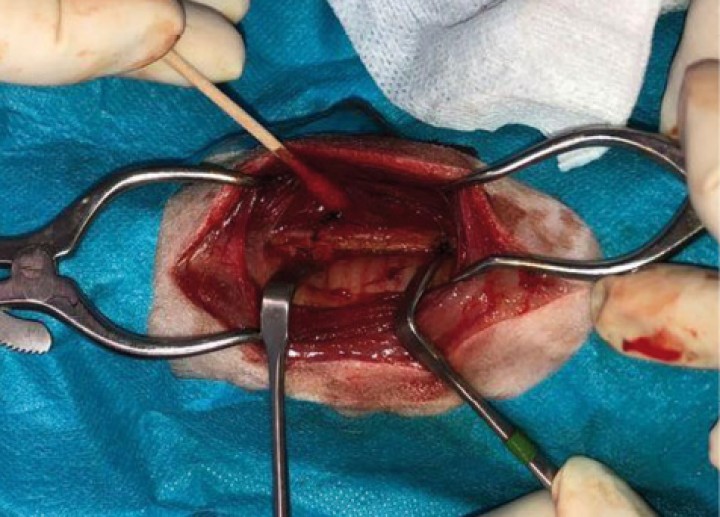

Al inicio de la cirugía (Figs. 8 y 9), durante la incisión de piel, se produjo una respuesta nociceptiva observándose una elevación de la PANI y la frecuencia respiratoria (FR) (<15 % de aumento de los valores anteriores), que se estabilizaron sin necesidad de rescate analgésico. Durante el resto de la cirugía, los parámetros se mantuvieron con variaciones mínimas dentro de los márgenes fisiológicos. Al finalizar el procedimiento, se administró meloxicam a 0,2 mg/kg IV (Metacam, Boehringer Ingelheim, Terrassa) y, considerando el carácter nervioso del paciente, dexmedetomidina a 1 µg/kg IV lento. Tras esto se procedió a la extubación de la tráquea del animal y su recuperación fue buena y sin complicaciones. La duración total del procedimiento desde la intubación hasta la extubación fue de 2,5 horas (Fig. 10).

<p>Abordaje quirúrgico de la región previa a exponer la neoplasia.</p>

Figura 8

Abordaje quirúrgico de la región previa a exponer la neoplasia.

<p>Imagen de la neoplasia durante el abordaje quirúrgico.</p>

Figura 9

Imagen de la neoplasia durante el abordaje quirúrgico.